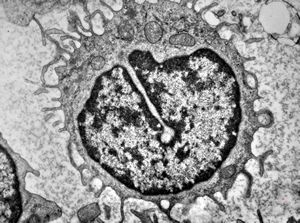

F,61y. | blood - lymphoplasmocellular leukemia